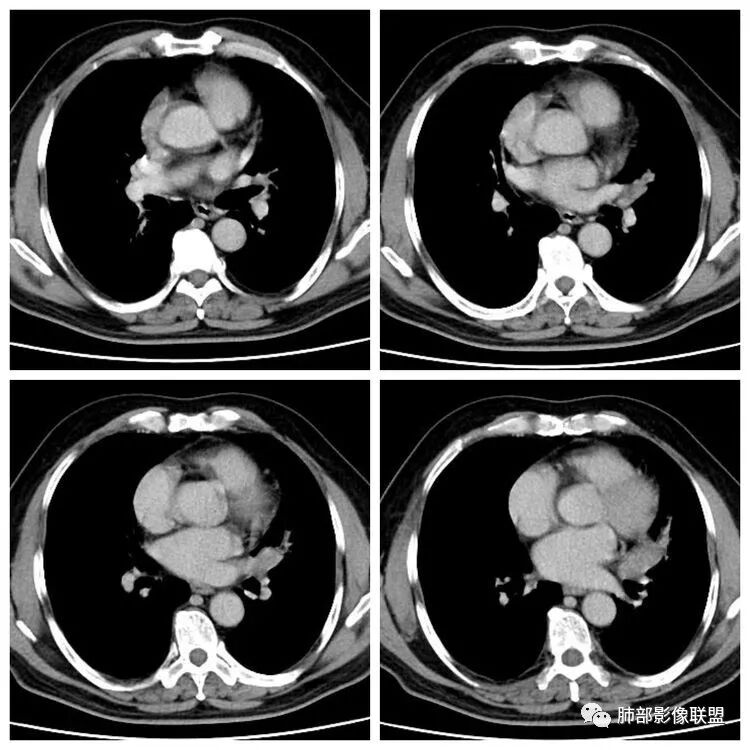

患者,男 ,66岁, “左肺占位”收住院。CEA   5.23 轻度增高

平扫 动脉期 静脉期  40HU、48HU、57HU

患者老年男性,“左肺占位”收入住院。查CEA轻度升高。胸部CT:左肺肺门占位并左肺下叶阻塞性,远端肺组织膨胀不全,增强可见轻度强化,内似见低密度灶。双肺多发类圆形结节,以左肺上叶尖后段为大,内可见部分钙化,边缘光滑、清楚。综合考虑恶性病变,鳞癌并转移可能大,鉴别腺癌、结核。

胸CT:左下叶内前基底段肿块,支气管堵塞,强化弱,延迟强化,两肺多处结节,右上肺门淋巴结大。常规考虑:肺癌可能 ,肺内小结节,转移?鉴别:错构瘤,TB等。

左肺下叶占位,左肺下叶前内支气管阻塞可疑(缺乏薄层),病灶有膨胀性,远端较内侧细,增强病灶强化不明显——乏血供病灶,病灶沿支气管生长,考虑恶性病变,左肺上叶可见小结节病灶,边缘光滑清晰,考虑转移瘤,综上所述考虑恶性病变,左肺下叶小细胞类癌可能,左肺上叶转移。

左肺下叶结节支气管进入截断,远端肺不张,增强后坏死不均匀,肺癌明显,至于病理类型,鳞癌,小细胞,腺癌都有支持和不支持的地方,个人倾向于鳞癌可能,理由,纵隔淋巴结肿大不明显,远端阻塞性不张,支持小细胞的地方,坏死呈沼泽样,但纵隔无明显淋巴结肿大及冰冻表现。腺癌这种表现一般为低分化腺癌,但远端阻塞性不张及纵隔无明显淋巴结肿大不支持。

1.定位:左肺块影同时累及下舌段及下叶内基底段且相互延续。病灶跨叶,或存在叶裂发育异常,或者说就是病灶的肺门蔓延。

2.病灶前上部分与舌段支气管相关且形成阻塞。

4.增强扫描左肺门区块影轻度强化,强化程度轻于舌段周围不张肺组织。

6.分析:男性患者,左肺门区块状影,支气管阻塞,强化不显著,未见淋巴结肿大,更多见于肺鳞癌。难以解释的是下肺病灶的生长方式。

沿肺门或是叶裂缺损孤立发生且蔓延,转移性腺癌似乎可以解释,但占据较大支气管腔就属罕见了。